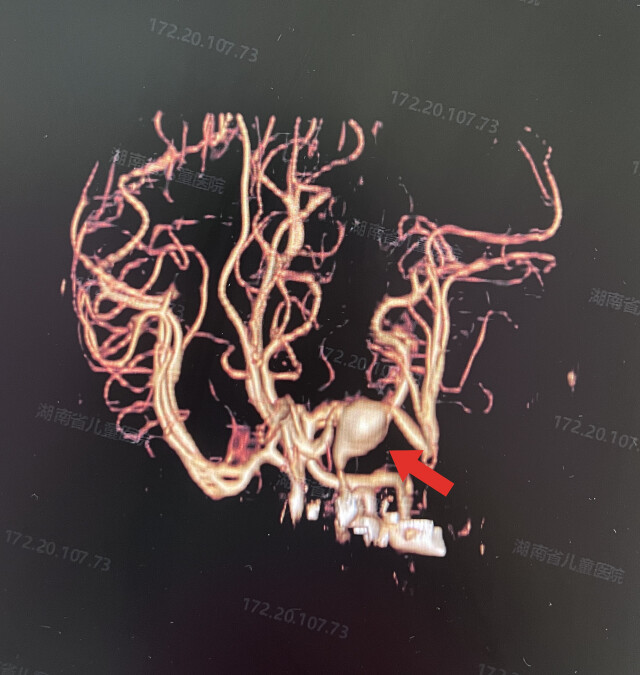

经湖南省儿童医院CT血管成像(CTA)检查,发现乐乐的左侧大脑中动脉M1段可见一巨大动脉瘤,直径约2厘米,且已破裂出血,情况十分危急。该院新生儿科、神经外科、麻醉手术科等多学科专家团队立即进行集中会诊。考虑到乐乐年龄小,血管纤细,不宜行介入治疗,开颅手术是目前唯一的治疗方法。

(术前CTA提示巨大动脉瘤)

8月14日,出生16天的乐乐被送入手术室,刘景平带领手术团队实施手术。由于乐乐已经发生一次动脉瘤破裂,大量暗红色陈旧性血凝块覆盖乐乐整个左侧大脑表面。刘景平在显微镜下仔细清除硬膜下、蛛网膜下腔及颈动脉池内血肿后,显露出颈内动脉,乐乐的颈内动脉直径约2毫米,颈内动脉上行分叉处有一巨大动脉瘤,大小约2.1*2厘米,周围可见血凝块并与脑组织粘连。刘景平用动脉瘤探针探查仔细分离动脉瘤,切除大部分瘤体,将动脉瘤塑形后永久动脉瘤夹夹闭。手术过程中,麻醉医生时刻关注,为生命安全保驾护航。历时9小时15分钟,手术终于顺利完成。术后,乐乐被送入新生儿监护病房,在多学科医护人员的悉心照料下,乐乐克服重重难关,目前病情逐渐稳定。